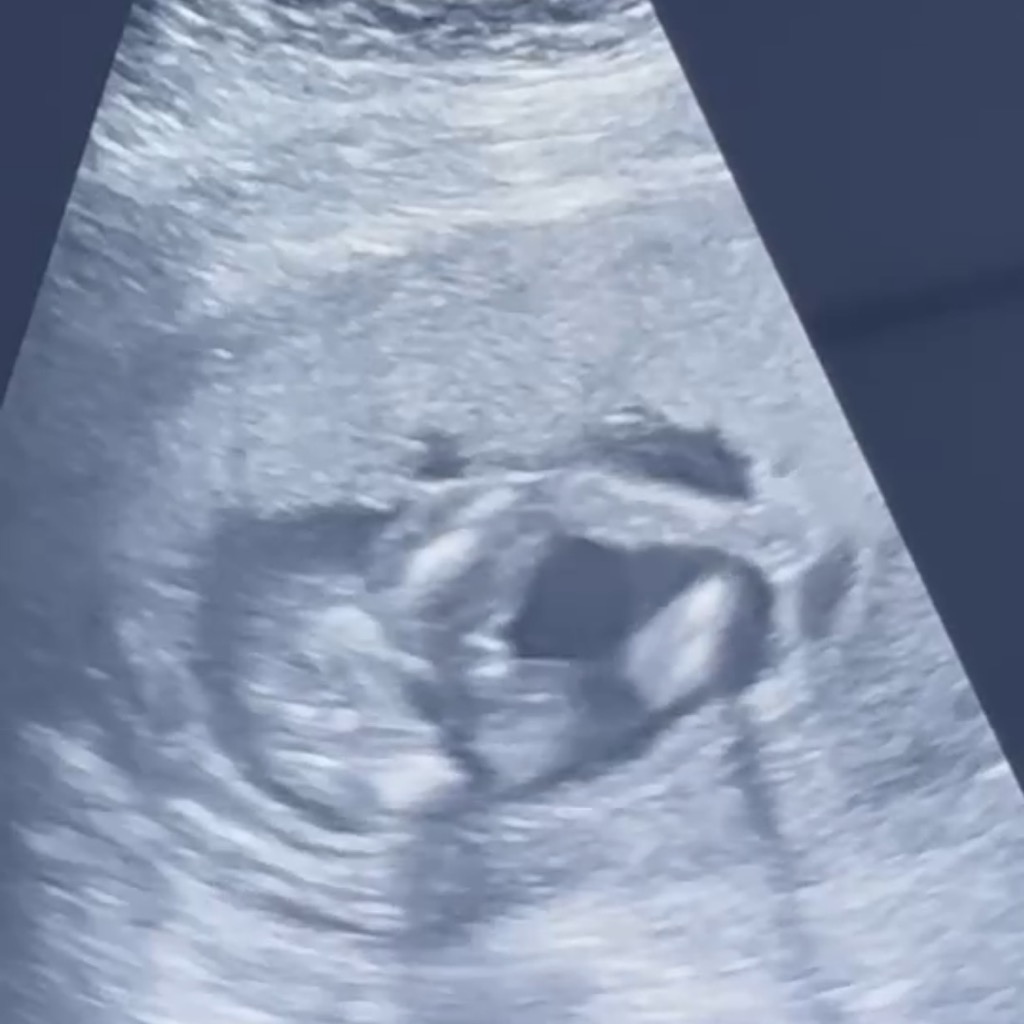

ช่วยดูหน่อยค่ะว่าเป็นเพศหญิงหรือเพศชาย

พอดีไปอัลตร้าซาวด์มาแล้วทีนี้หมอบอกว่าหมอดูไม่ออกว่าผู้หญิงหรือผู้ชายเพราะน้องหนีบขาไว้ ได้รูปมาเลยอยากรู้ว่าคล้ายผู้หญิงหรือผู้ชายมากกว่ากันคะ